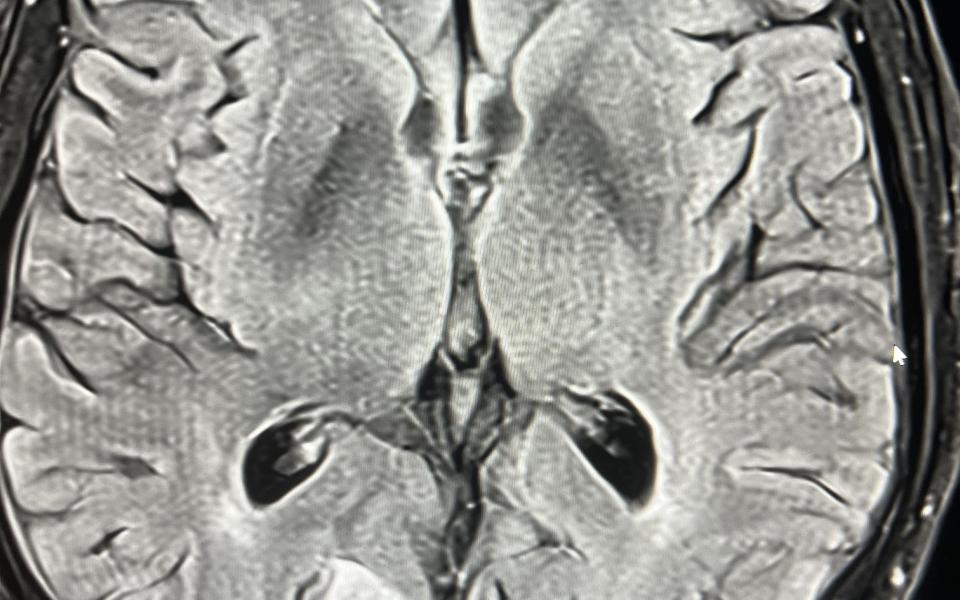

76 Male with bilateral elevated IOP to 50mmHg and loss of vision over 4 months to HM. Gonioscopy demonstrated extensive deposition of hamartomatous lesions, resulting in secondary angle closure.